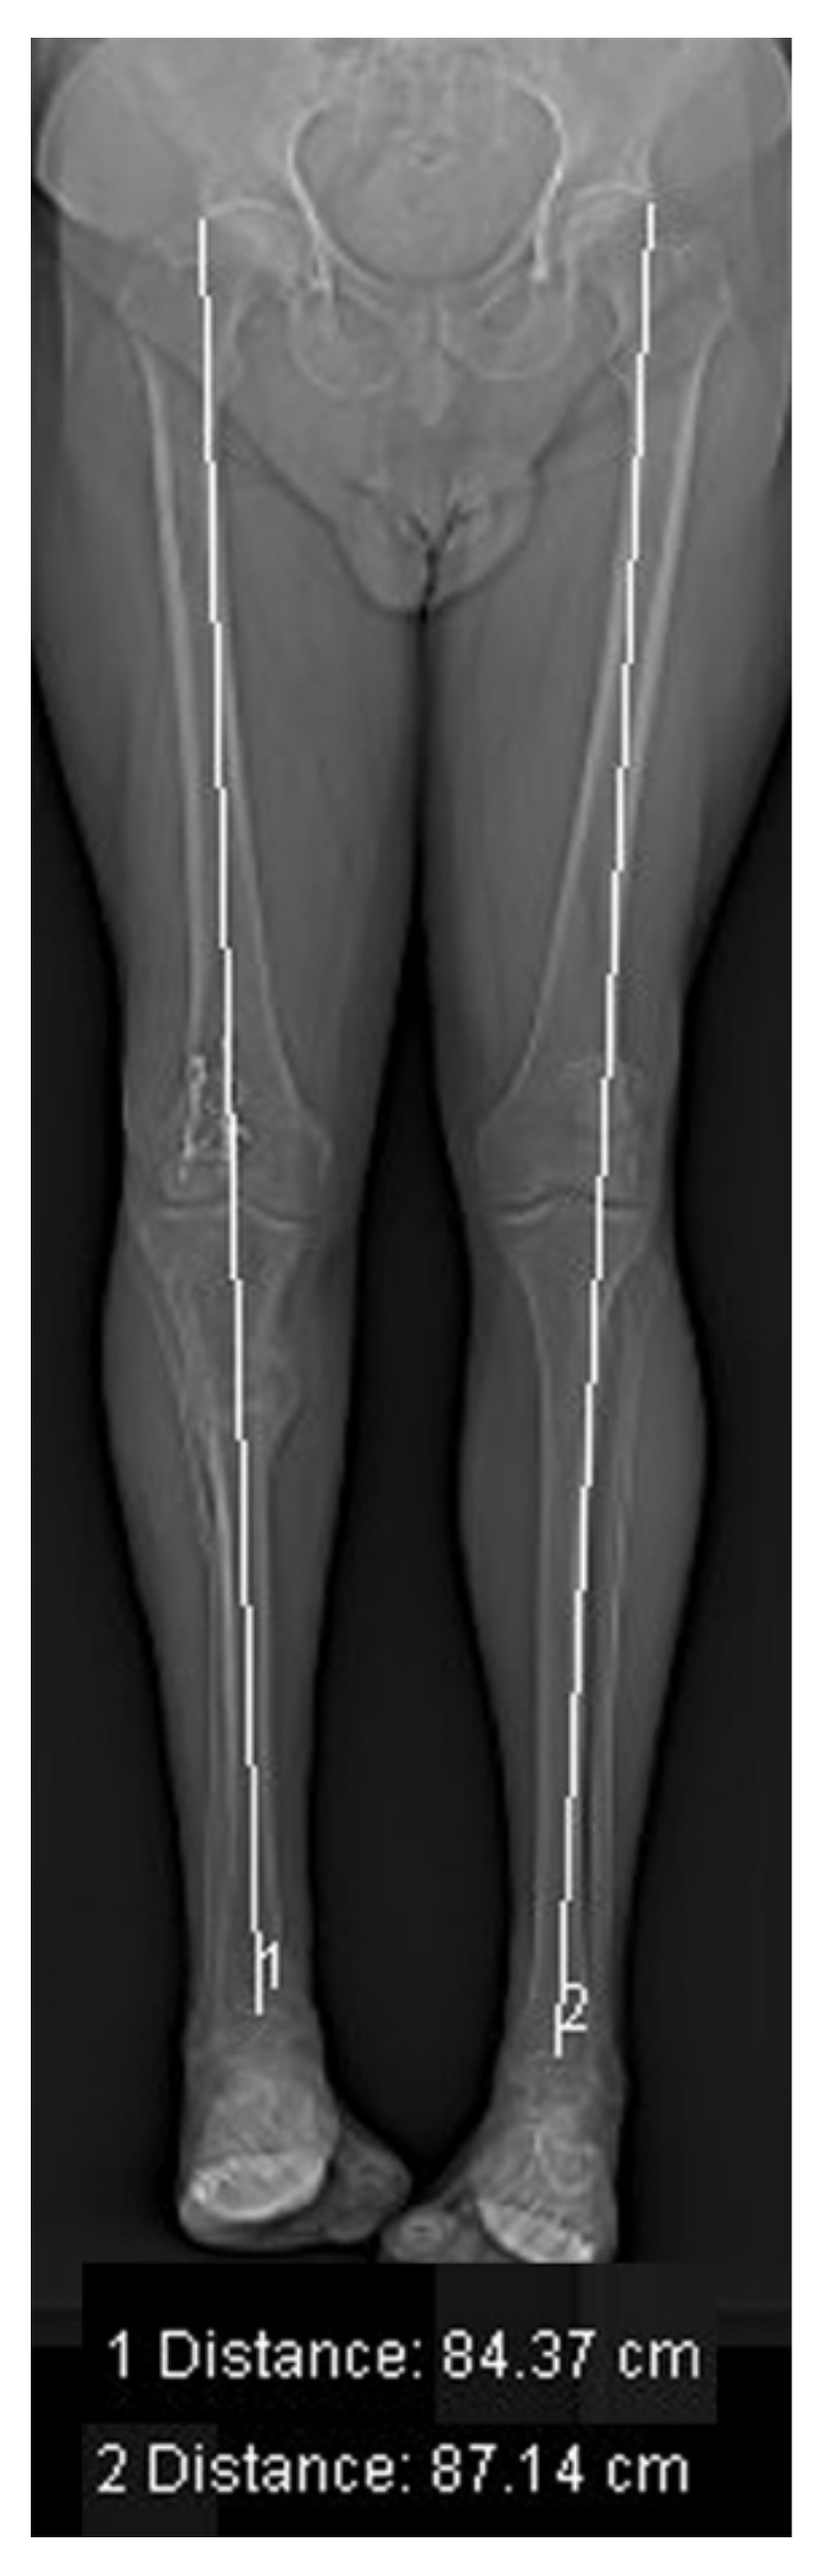

2.4.5. Leg Length Measurement

| LLD | Limb length discrepancy |